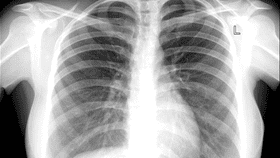

A 27-year-old woman showed up to hospital with a cough, fever, and thick mucus that had been persistent for six months. Four months prior to attending hospital, she had been prescribed antibiotics and anti-tuberculosis treatment, which appeared to have no impact on her symptoms, doctors write in a case report published in the National Library of Medicine.

The school teacher's sputum was tested for TB and was found to be negative. However, when her chest was scanned they found a lesion in the right upper lobe of her lungs. Upon further investigation, it appeared to be "an inverted bag-like structure ‘sitting’ in the bronchus".